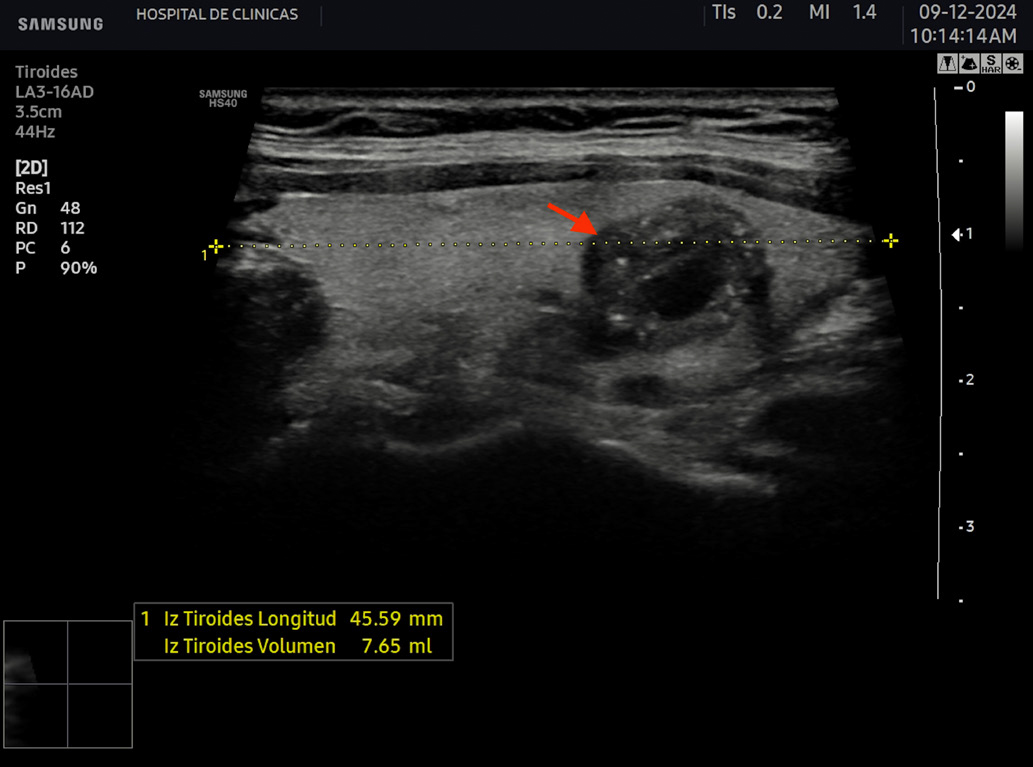

La hipoecogenicidad del parénquima glandular se correlaciona con el grado de infiltración linfocitaria, atrofia de los folículos y disminución del contenido coloide. Esto genera menos reflexión de las ondas sonoras y, por lo tanto, menor ecogenicidad6. Se puede encontrar además aspecto micro o macronodular. Se denominan seudonódulos a las áreas de intensa infiltración linfocitaria local, las cuales deben ser diferenciadas de los nódulos verdaderos que requieren otro seguimiento6. En la figura 6 se aprecian estas características comentadas.

Figura 6: Corte transversal y longitudinal de tiroides de paciente con tiroiditis de Hashimoto. Se señala la disminución de la ecogenicidad, estructura

heterogénea, seudonodular.